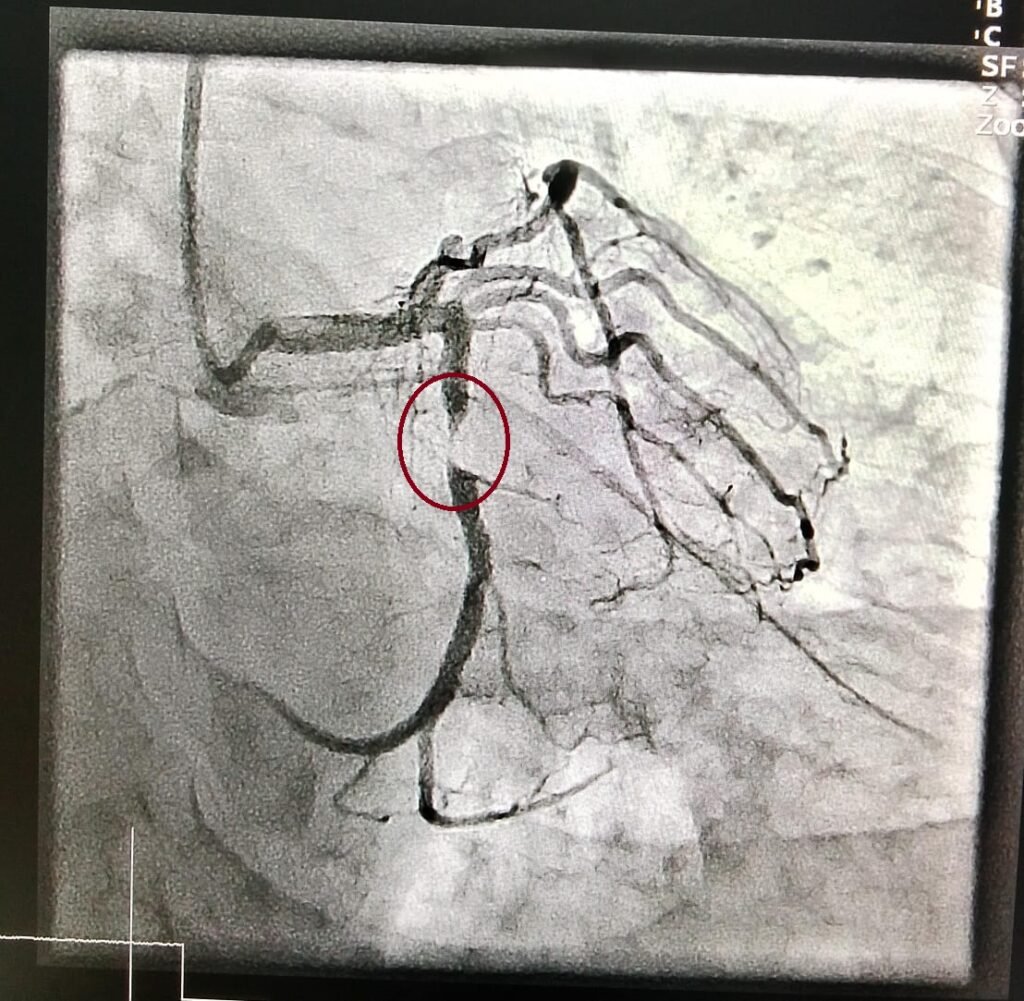

Coronary Angiography is a minimally invasive procedure that allows doctors to visualize the blood vessels of the heart to detect blockages, narrowing, or other issues. It is the gold standard diagnostic tool for assessing coronary artery disease and is typically performed when a patient exhibits symptoms like chest pain, shortness of breath, or unexplained fatigue. Angiography involves injecting a contrast dye into the coronary arteries and taking X-ray images to reveal any obstructions or irregularities in blood flow.

The process is performed in a specialized unit known as the catheterization lab or cath lab. During the procedure, a thin, flexible tube called a catheter is inserted into a blood vessel, typically in the wrist or groin, and guided to the coronary arteries. The dye is injected through the catheter, allowing the arteries to be seen clearly on the X-ray images. This helps doctors determine the severity and location of any blockages or narrowing in the arteries.

Angioplasty, also known as percutaneous coronary intervention (PCI), is an advanced procedure used to treat coronary artery disease by opening up blocked or narrowed arteries. The goal of angioplasty is to restore normal blood flow to the heart by removing obstructions that restrict the flow of oxygen-rich blood to the heart muscle. Angioplasty is often performed after coronary Angiography has revealed a significant blockage.

During angioplasty, a balloon catheter is inserted into the blocked artery. Once in place, the balloon is inflated to open up the narrowed area. In some cases, a stent—a small, mesh-like tube—is placed at the site of the blockage to help keep the artery open. This procedure is highly effective in relieving chest pain (angina), reducing the risk of heart attacks, and improving the overall quality of life for patients who have coronary artery disease.